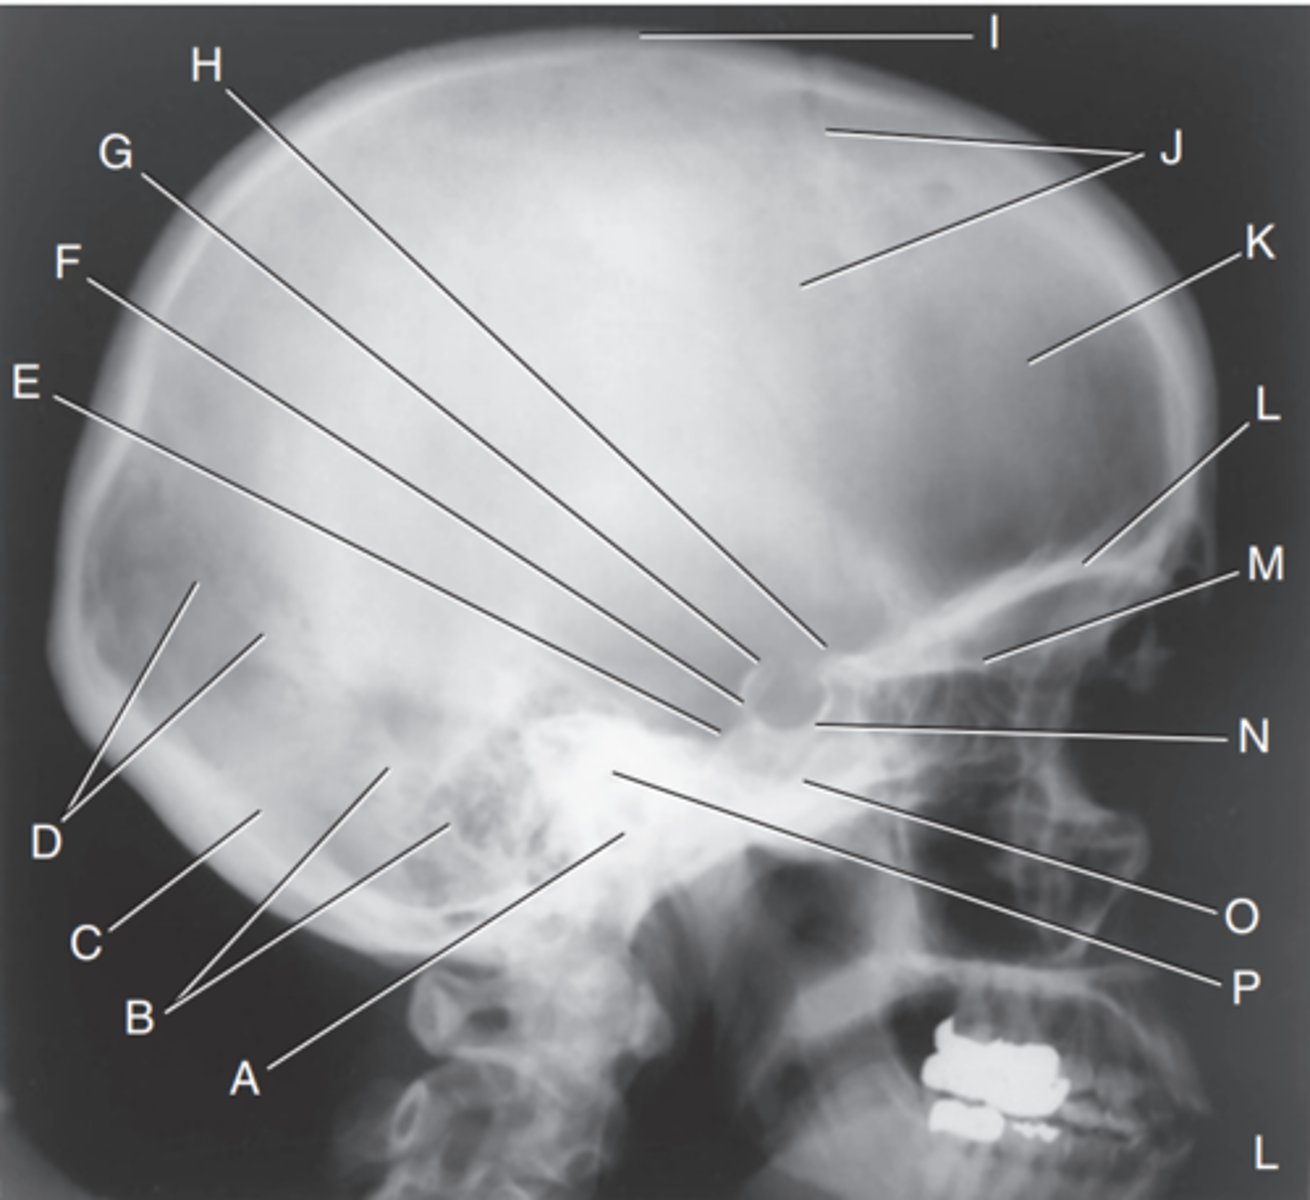

EAM

Label A

Mastoid portion of temporal bone

Label B

Occipital bone

Label C

Lambdoidal suture

Label D

Clivus

Label E

Dorsum sellae

Label F

Posterior clinoid processes

Label G

Anterior clinoid processes

Label H

Vertex of cranium

Label I

Coronal suture

Label J

Frontal bone

Label K

Orbital plates

label L

Cribriform plate

Label M

Sella turcica

Label N

Body of sphenoid (sphenoid sinus)

Label O

Petrous portion of temporal bone

Label P